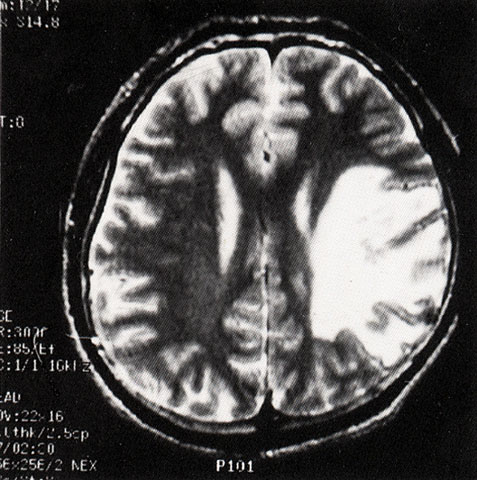

FH1044 脑炎性感染(MRI)

光盘检索编码 FH1044  函授作业图编号 1044

图  名 脑炎性感染(MRI)